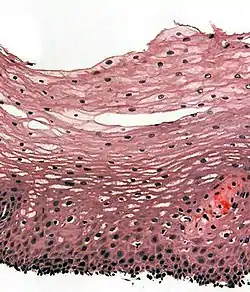

![]() Section of the human skin showing the stratified squamous epithelial surface, referred to as the epidermis. The layer of keratin here is named the stratum corneum. | |

A stratified squamous epithelium consists of squamous (flattened) epithelial cells arranged in layers upon a basal membrane. Only one layer is in contact with the basement membrane; the other layers adhere to one another to maintain structural integrity. Although this epithelium is referred to as squamous, many cells within the layers may not be flattened; this is due to the convention of naming epithelia according to the cell type at the surface. In the deeper layers, the cells may be columnar or cuboidal.[1] There are no intercellular spaces. This type of epithelium is well suited to areas in the body subject to constant abrasion, as the thickest layers can be sequentially sloughed off and replaced before the basement membrane is exposed. It forms the outermost layer of the skin and the inner lining of the mouth, esophagus and vagina.[2]

In the epidermis of skin in mammals, reptiles, and birds, the layer of keratin in the outer layer of the stratified squamous epithelial surface is named the stratum corneum. Stratum corneum is made up of squamous cells which are keratinized and dead. These are shed periodically.